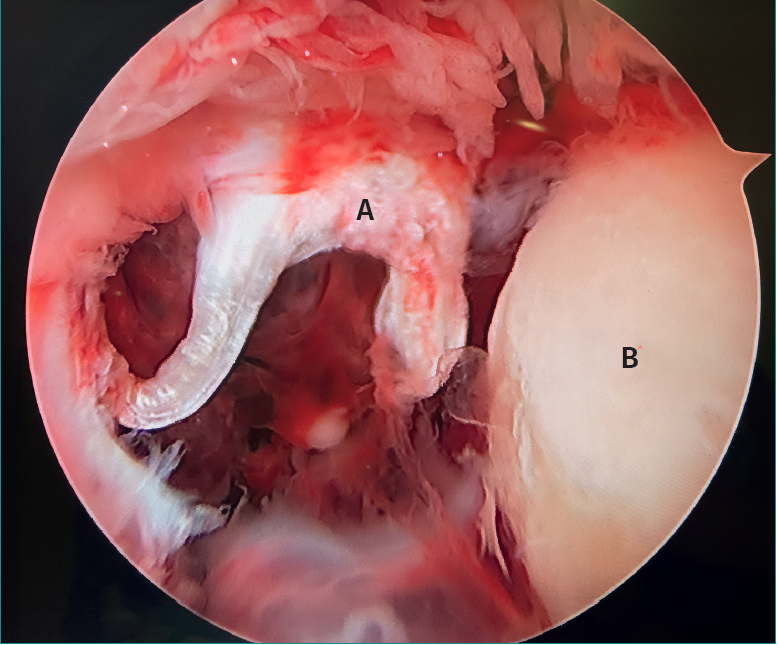

La letra pi en el tobillo

The letter pi on the ankle